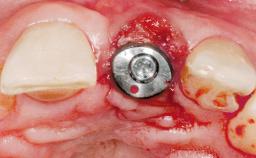

Immediate Flapless Placement of an Implant in a Maxillary Right Lateral Incisor Site

This 43-year-old male patient, a non-smoker, came to our practice because of a fracture of tooth 12 caused by a bicycle accident. Due to the combined para- and infrabony crown and root fracture, tooth extraction, and subsequent implant placement were suggested to the patient as the therapy of choice. The patient had high esthetic expectations with regard to the treatment outcome and asked for an immediate fixed provisional restoration. His individual esthetic risk profile summed up to a medium esthetic risk.

# of Implants 1

Type of Implants Two-Piece

Placement Protocol Immediate implant placement

Tooth Site Maxillary incisor or canine

Socket Morphology Single-root socket

Socket Integrity Sufficient, with intact bone walls

Bone Volume Sufficient, with intact walls